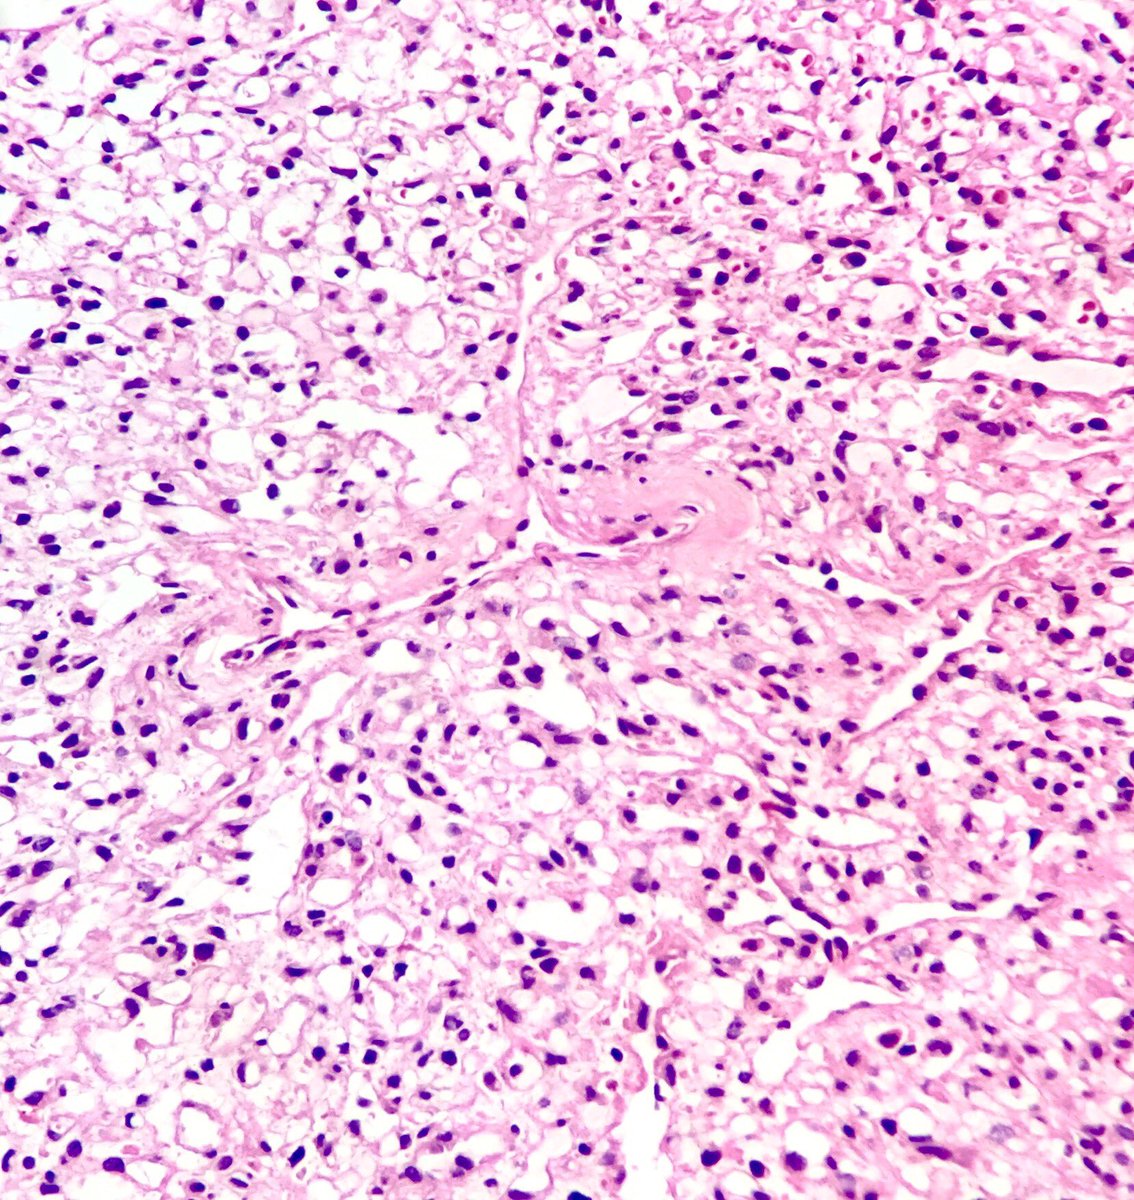

Two very different histologic patterns in the exact same pituitary adenoma.

#pathology#neuropath#pituitary#adenomapic.twitter.com/GKO6yLBrw7